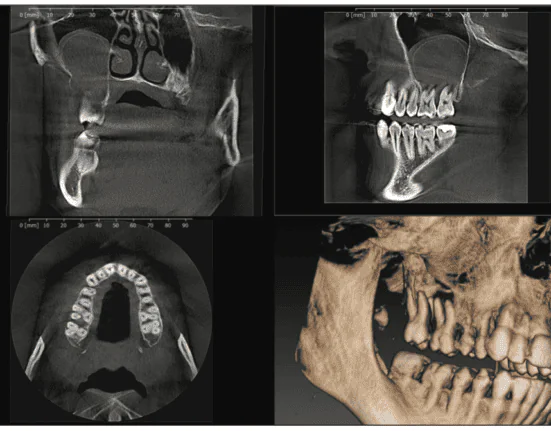

Within seconds, the CBCT radiographs were on my monitor, revealing that this case was far from routine. The 3D radiographs showed a very large mass, about 1 inch in diameter, above teeth Nos. 2 and 3, entering the sinus with no bone surrounding it. Diagnosing this mass was beyond a general dentist’s scope of practice. Moreover, if these teeth were simply extracted, there would be a 19-mm oral/antral communication between the sinus and the mouth. The CBCT scans were essential in preventing a disaster (Figure 2).